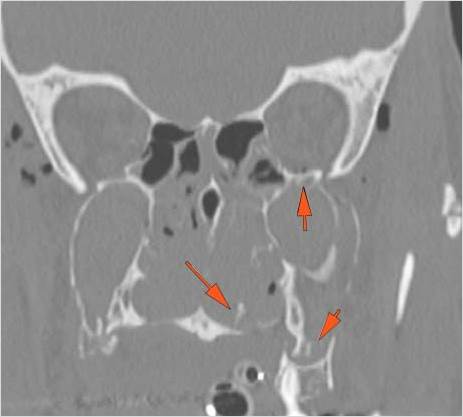

The alveolar ridge, premaxilla, and/or the palatine process of the maxillary bones on either side are fractured. [Yes/No]

The hard palate is fractured. [Yes/No]

The pterygoid processes of the sphenoid bone are fractured. [Yes/No]

The the zygomatic arch, frontozygomatic suture or infraorbital rim are fractured. [Yes/No]

The lateral wall of the orbit is fractured. [Yes/No]